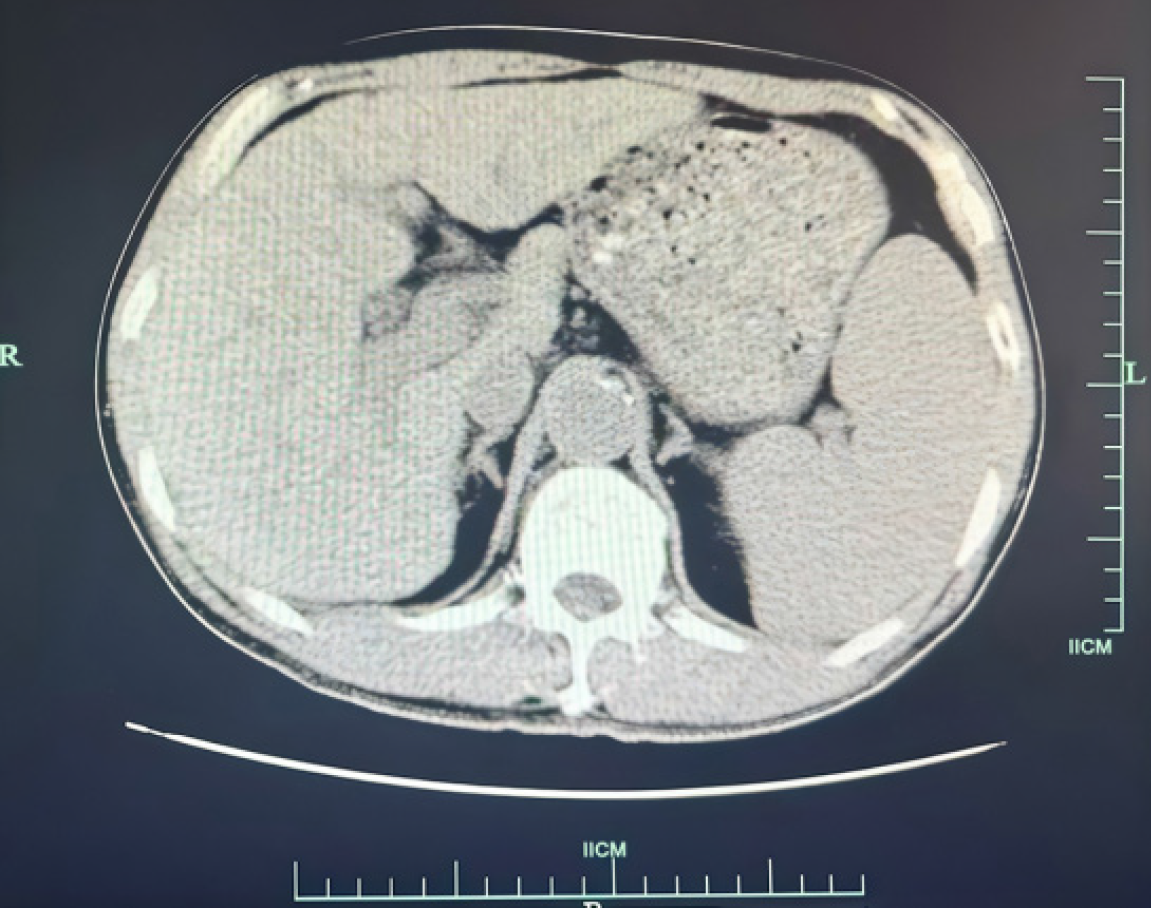

An upper-abdominal CT scan performed on March 22, 2022, demonstrated findings consistent with cholecystitis and multiple gallstones. In addition, a potential communication was noted between the gallbladder fundus and the gastric antrum. Several gallstones were identified in the gastric antrum, along with mild periantral fluid accumulation and multiple small regional lymph nodes. A small volume of perihepatic fluid was also detected (Figure 1).

Figure 1

Figure 1 This computed tomography image is the abdominal cross-sectional image of this patient on March 22, 2022. In the image, an oval high-density gallstone (about 5.0 cm in diameter) was embedded in the proximal duodenum, resulting in significant expansion of the stomach. Edema of duodenal wall and local intestinal lumen stenosis can be seen around the stone. In addition, the gas shadow in the gallbladder suggests that there may be abnormal channels between the gallbladder floor and the gastric antrum, with a little exudation around the gastric antrum.